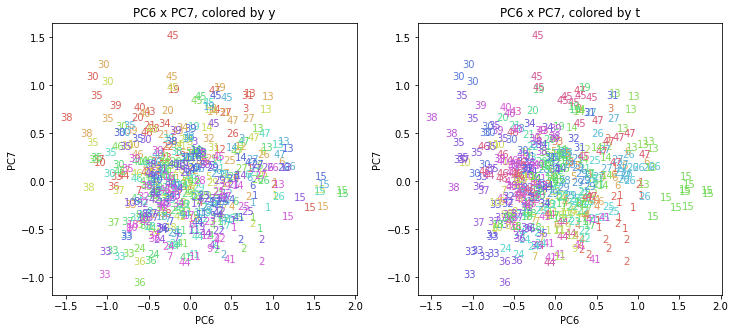

PCAの結果の第n主成分をPCnと表記します。

医療費データの場合と同様に、PCAの結果を見やすく表示するため、seabornのカラーパレットを使って、年月別、都道府県別に色分けして図示してみます(左側が年月別に色分け、右側が都道府県別に色分け)。PC1~PC8まで表示しました。

都道府県番号の表示

上の色分けだけでは都道府県が区別しにくいので、医療費データの場合と同様に、点の代わりに都道府県番号をプロットした図も描いておきます(色分けは上と同じ)。

医療費データの場合ほどはっきりとはしていませんが、PC2が概ね時間の経過を表す成分で、残りの成分が時点によって変わらない地域の特徴を表す成分となっているようです。

また、PC1×PC3を見ると、47沖縄が他の都道府県からかなり離れたところに位置しており、沖縄の地域差が際立っているのが分かります。これは、以前別の記事で年齢階級のない健診データでPCAを実行した場合と似た結果となっています。